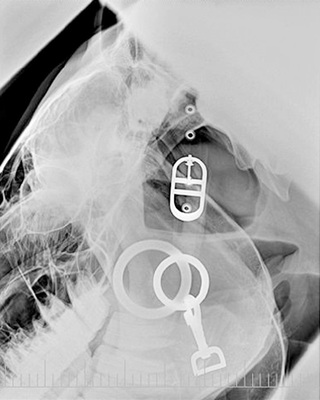

The patient should be clean and free of any debris. If the hair coat of the patient is wet or full of debris, confusing artifacts can appear on the radiograph. Collars, harnesses, and leashes of any sort, especially those made of metal, should be removed (Fig. 15.5). Remove bandages, splints, and casts before radiography unless there is a definite medical reason for leaving them in place. Pedal radiography of the horse may require removing the shoe and cleaning the frog of the foot to minimize any artifacts that may obscure an area of interest.